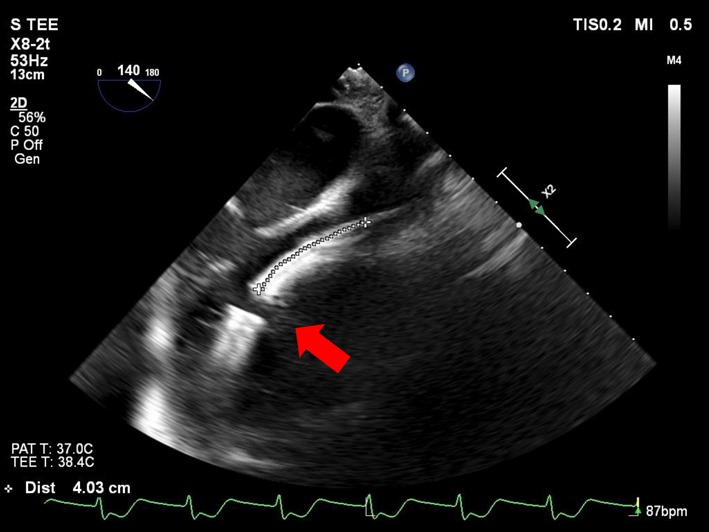

Impella®循環補助用心内留置型ポンプカテーテル(Impella® CP)と静動脈型体外式膜型人工肺により劇症型心筋炎の左室unloadingが著効した12歳男子例—体格の小さい患者における管理上の注意点A 12-year-old male case of successful left ventricular unloading utilizing Impella CP® and veno-arterial extracorporeal membrane oxygenation due to fulminant myocarditis—Precautions for management in patients with small stature